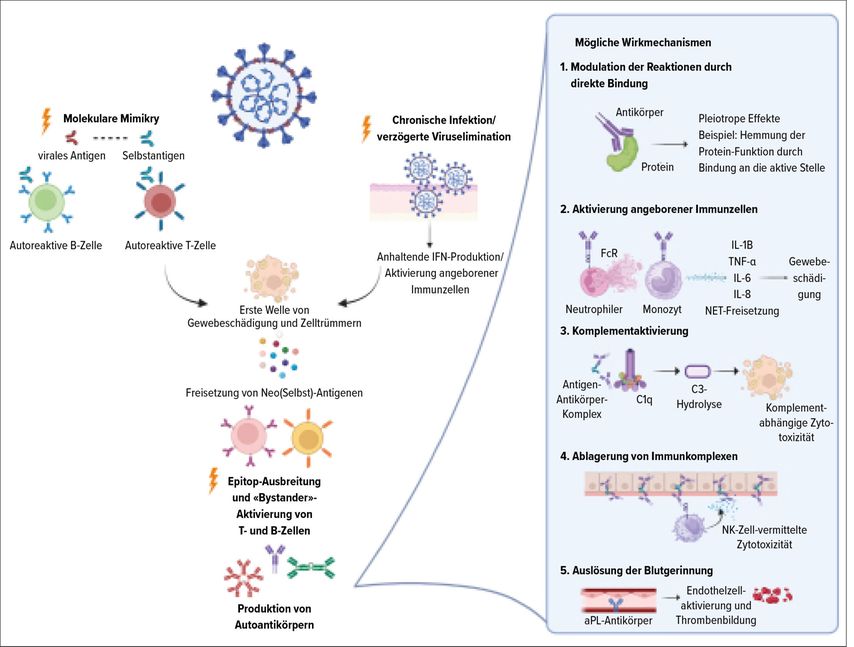

Molekular liessen sich zahlreiche Assoziationen zwischen Genloci sowie molekularen und zellulären Immunkomponenten und einer Covid-19-Infektion ableiten; das Immunsystem war also nicht unbeeinflusst, bei den meisten Patienten reichten die Gegenregulationsmechanismen jedoch für eine Selbstheilung (Abb. 1).7,8

Abb. 1: Modell zur Entwicklung von Autoimmunität nach Virusinfektion (mod. nach Talwar S et al. 2025)8